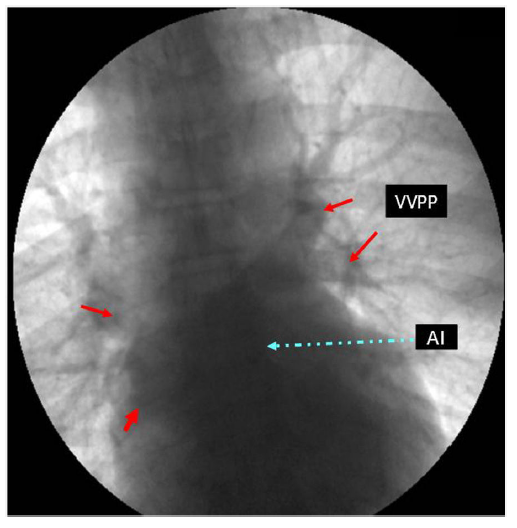

El cateterismo cardíaco izquierdo y derecho reportó lesiones graves en tres coronarias (descendente anterior, circunfleja y coronaria derecha). Presión de ventrículo izquierdo: 140/12mm Hg. Presión de aorta 140/80mm Hg. No existe gradiente de presión entre aorta y ventrículo izquierdo. Arteriografía pulmonar normal, buen retorno venoso a aurícula izquierda, presión de arteria pulmonar: 32/9mm Hg, con una media de 14mm Hg, presión en cuña de arteria pulmonar 9mm Hg (fig. 3). En el cateterismo derecho no reportó comunicación interauricular u otras malformaciones congénitas asociadas.

Figura 3 Cateterismo cardíaco que muestra el retorno venoso a la aurícula izquierda sin que se observen estructuras internas definidas tipo membrana. VVPP: venas pulmonares; AI: aurícula izquierda.